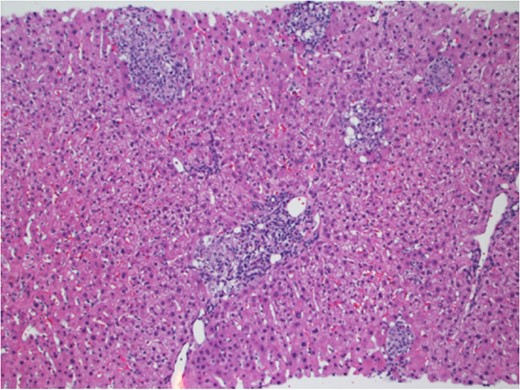

In March 2017, the patient presented with 2 weeks of generalized body aches, fevers, mild congestion and dysuria. His transaminases worsened—AST 360 U/L, ALT 387 U/L. Blood, urine and sputum cultures grew no organisms and the patient had a normal chest radiograph and abdominal ultrasound. CT sinus, obtained to rule out sinusitis, remarked on few mucous retention cysts of the maxillary sinuses, but was otherwise negative for any other pathology. However, further interrogation found that the patient had significant opportunistic infection exposure risk; the patient was a butcher at a local grocery store, and owned a new rabbit, several parakeets and four dogs. A repeat liver biopsy was performed, and this time, was found to have predominantly lobular, and occasionally portal, epithelioid granulomas (Fig. 1) with intracellular yeast-like elements (Fig. 2). These were described as narrow-based budding yeasts favoring histoplasma (Fig. 3). No portal based features of acute rejection were noted and bile ducts were preserved in the majority of portal tracts. Urine histoplasma antigen testing corroborated the histology finding—the patient had progressive disseminated histoplasmosis manifested as granulomatous hepatitis. He completed an 11-day course of liposomal amphotericin B and will continue itraconazole therapy for a year. His immunosuppression regimen was significantly decreased and mycophenolate was stopped. The most recent liver biopsy in May 2017 revealed a persistent—though significantly decreased—lobular inflammation, microgranulomas and budding yeast elements. His transaminases remain elevated at AST 265 U/L and ALT 259 U/L. He will continue close follow up to ensure further improvement on current therapy and resolution of Histoplasmosis.

Portal granuloma with histiocytes containing multiple intracytoplasmic yeast-like fungi. Hematoxylin and Eosin stain ×400.